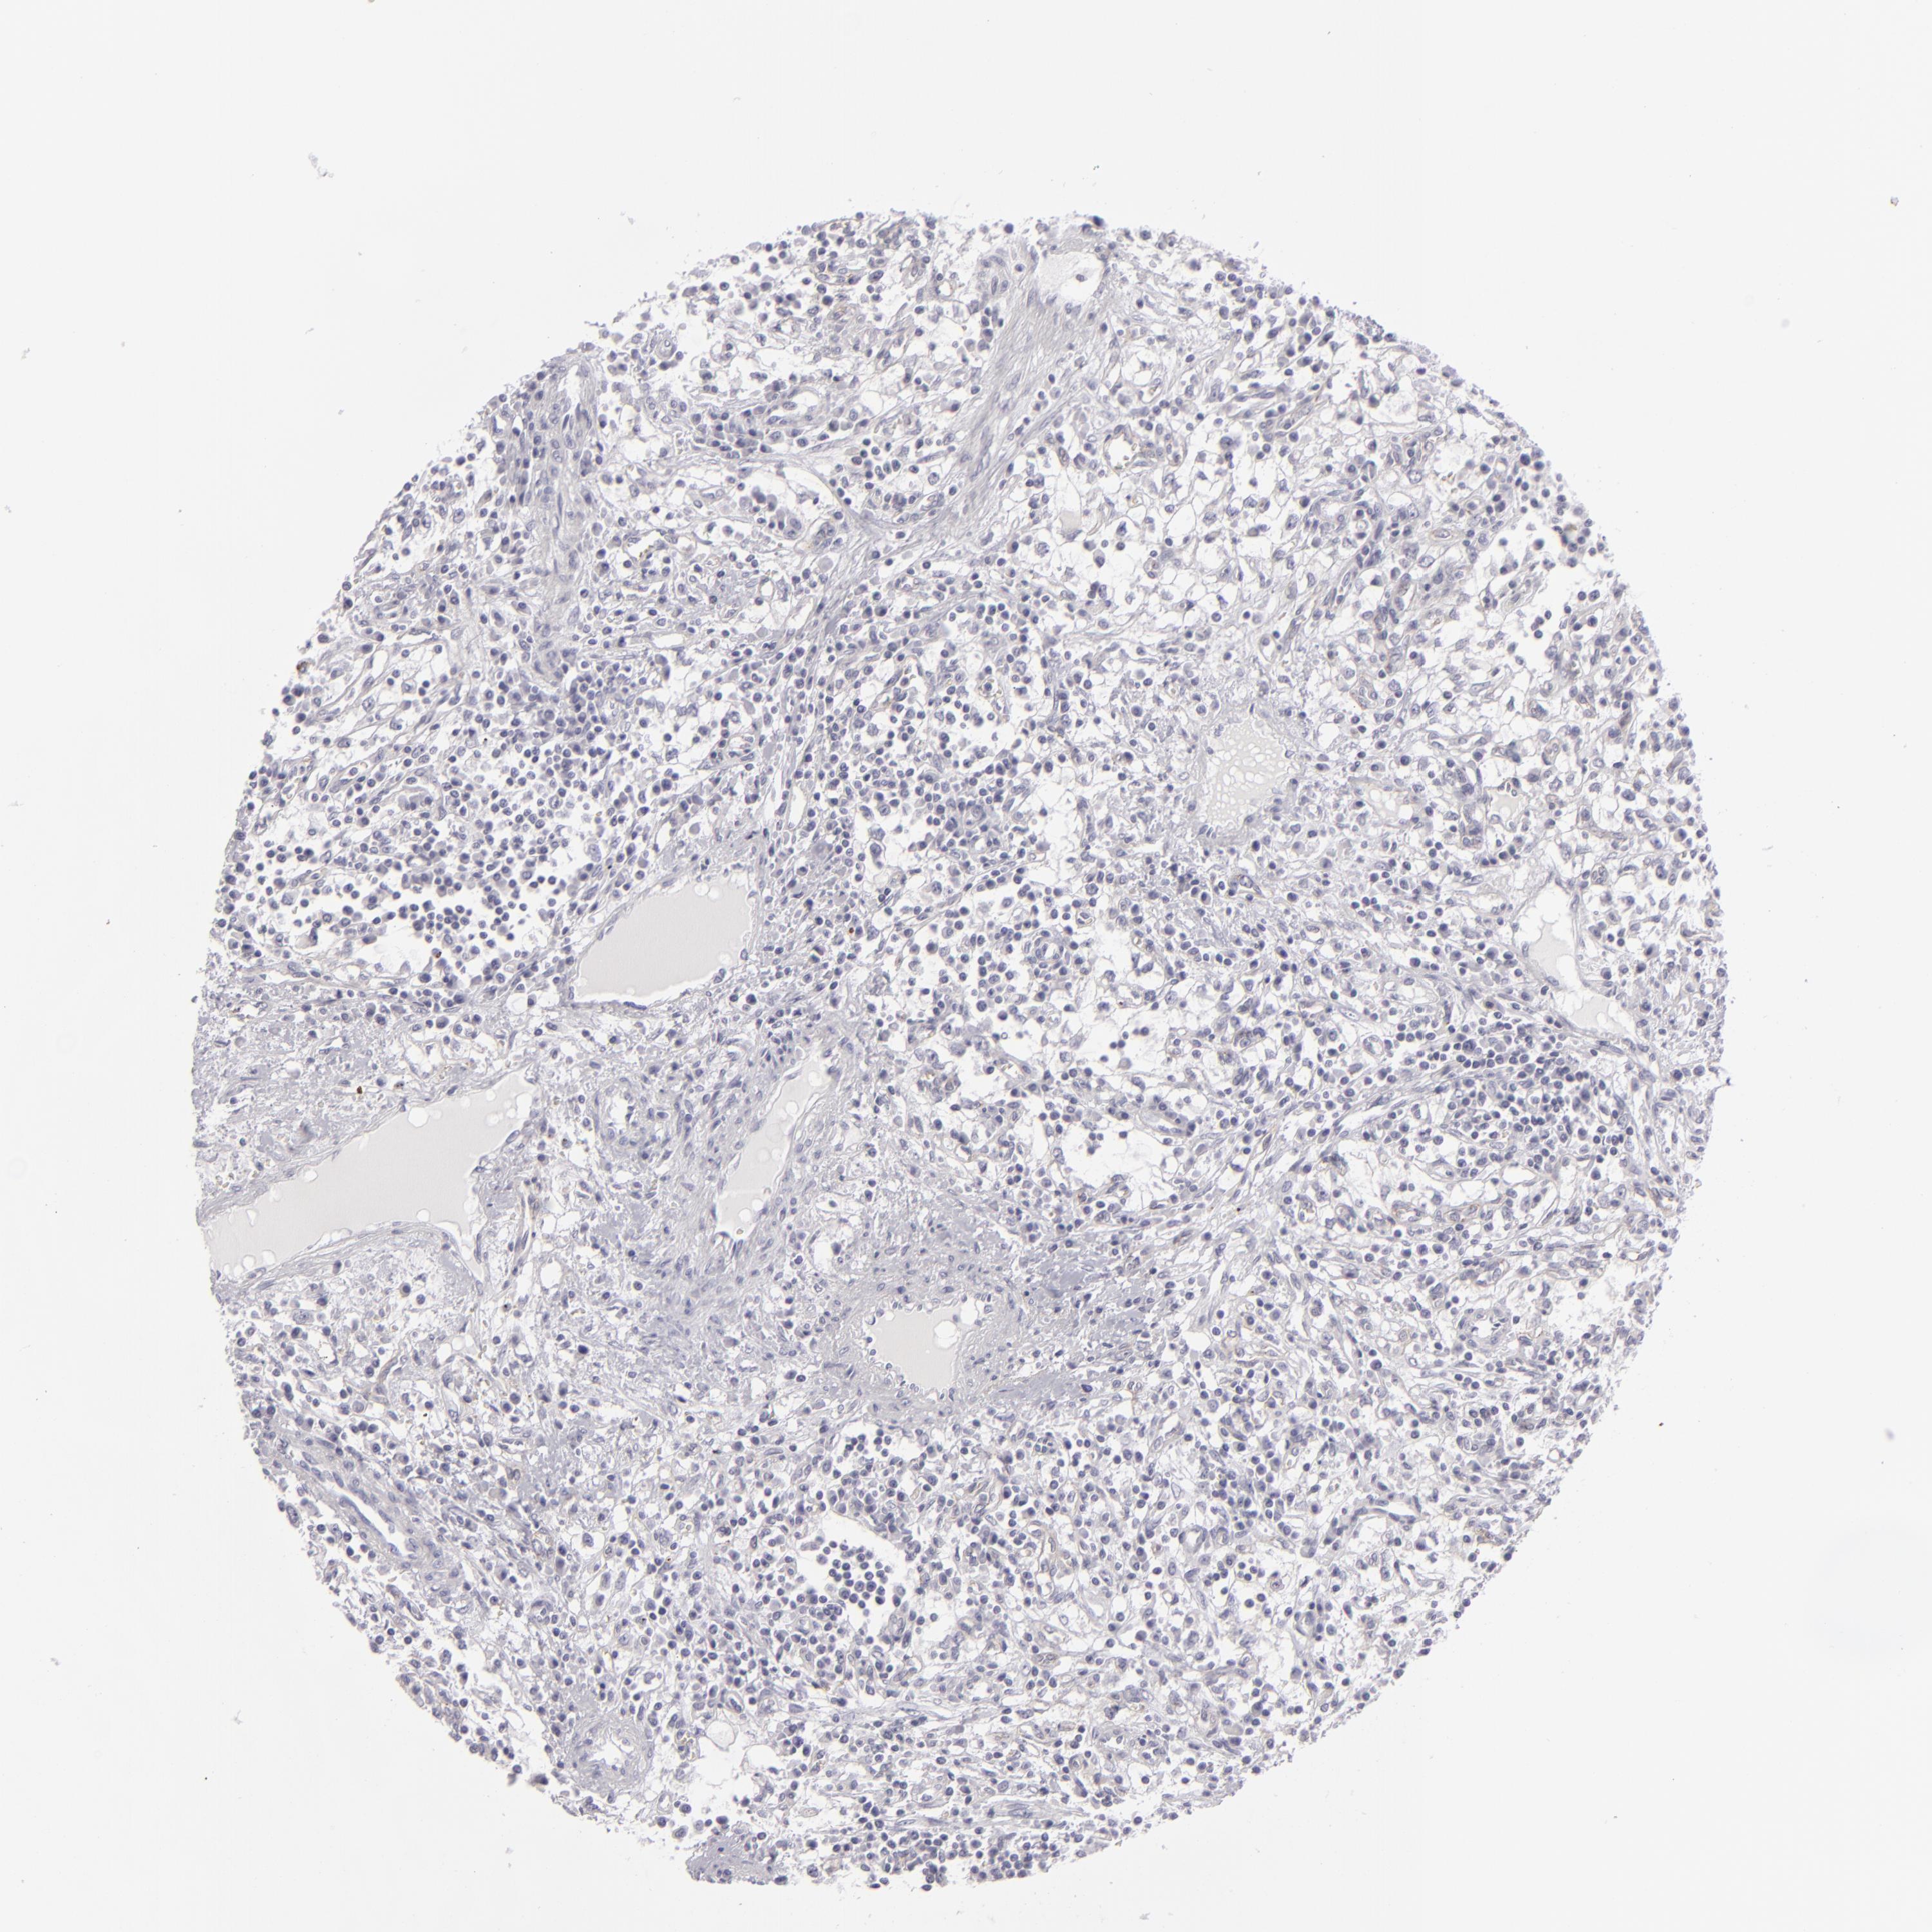

KIDNEY RENAL PAPILLARY CELL CARCINOMA (TCGA) - Interactive survival scatter ploti

The Survival Scatter plot shows the clinical status (i.e. dead or alive) for all individuals in the patient cohort, based on the same data that underlies the corresponding Kaplan-Meier plots. Patients that are alive at last time for follow-up are shown in blue and patients who have died during the study are shown in red.

The x-axis shows the expression levels (FPKM) of the investigated gene in the tumor tissue at the time of diagnosis. The y-axis shows the follow-up time after diagnosis (years). Both axes are complimented with kernel density curves demonstrating the data density over the axes. The top density plot shows the expression levels (FPKM) distribution among dead (red) and alive patients (blue). The right density plot shows the data density of the survived years of dead patients with high and low expression levels respectively, stratified using the cutoff indicated by the vertical dashed line through the Survival Scatter plot. This cutoff is automatically defined based on the FPKM cutoff that minimizes the p-score. The cutoff can be changed by dragging the vertical line or by entering a cutoff value in the square labeled "Current cut-off".

Under the Survival Scatter plot the p-score landscape (black curve; left axis) is shown together with dead median separation (red curve; right axis). Dead median separation is the difference in median mRNA expression between patients who have died with high and low expression, respectively. It is calculated as follows: median FPKM expression of dead patients with high expression - median FPKM expression of dead patients with low expression. This is intended to aid the user in visually exploring custom cutoffs and the associated p-scores and dead median separation.

Individual patient data is displayed and can be filtered by clicking on one or more of the category buttons on the top of the page. Categories describing expression level and patient information include: high, low, alive, dead, female, male and tumor stages. The scale of the x-axis can be toggled between linear and log-scale by clicking on the "x log" button. Mouse-over function shows TCGA ID, patient information and mRNA expression (FPKM) for each patient.

& Survival analysisi

Kaplan-Meier plots summarize results from analysis of correlation between mRNA expression level and patient survival. Patients were divided based on level of expression into one of the two groups "low" (under cut off) or "high" (over cut off). X-axis shows time for survival (years) and y-axis shows the probability of survival, where 1.0 corresponds to 100 percent.

JUP is not prognostic in Kidney Renal Papillary Cell Carcinoma (TCGA)